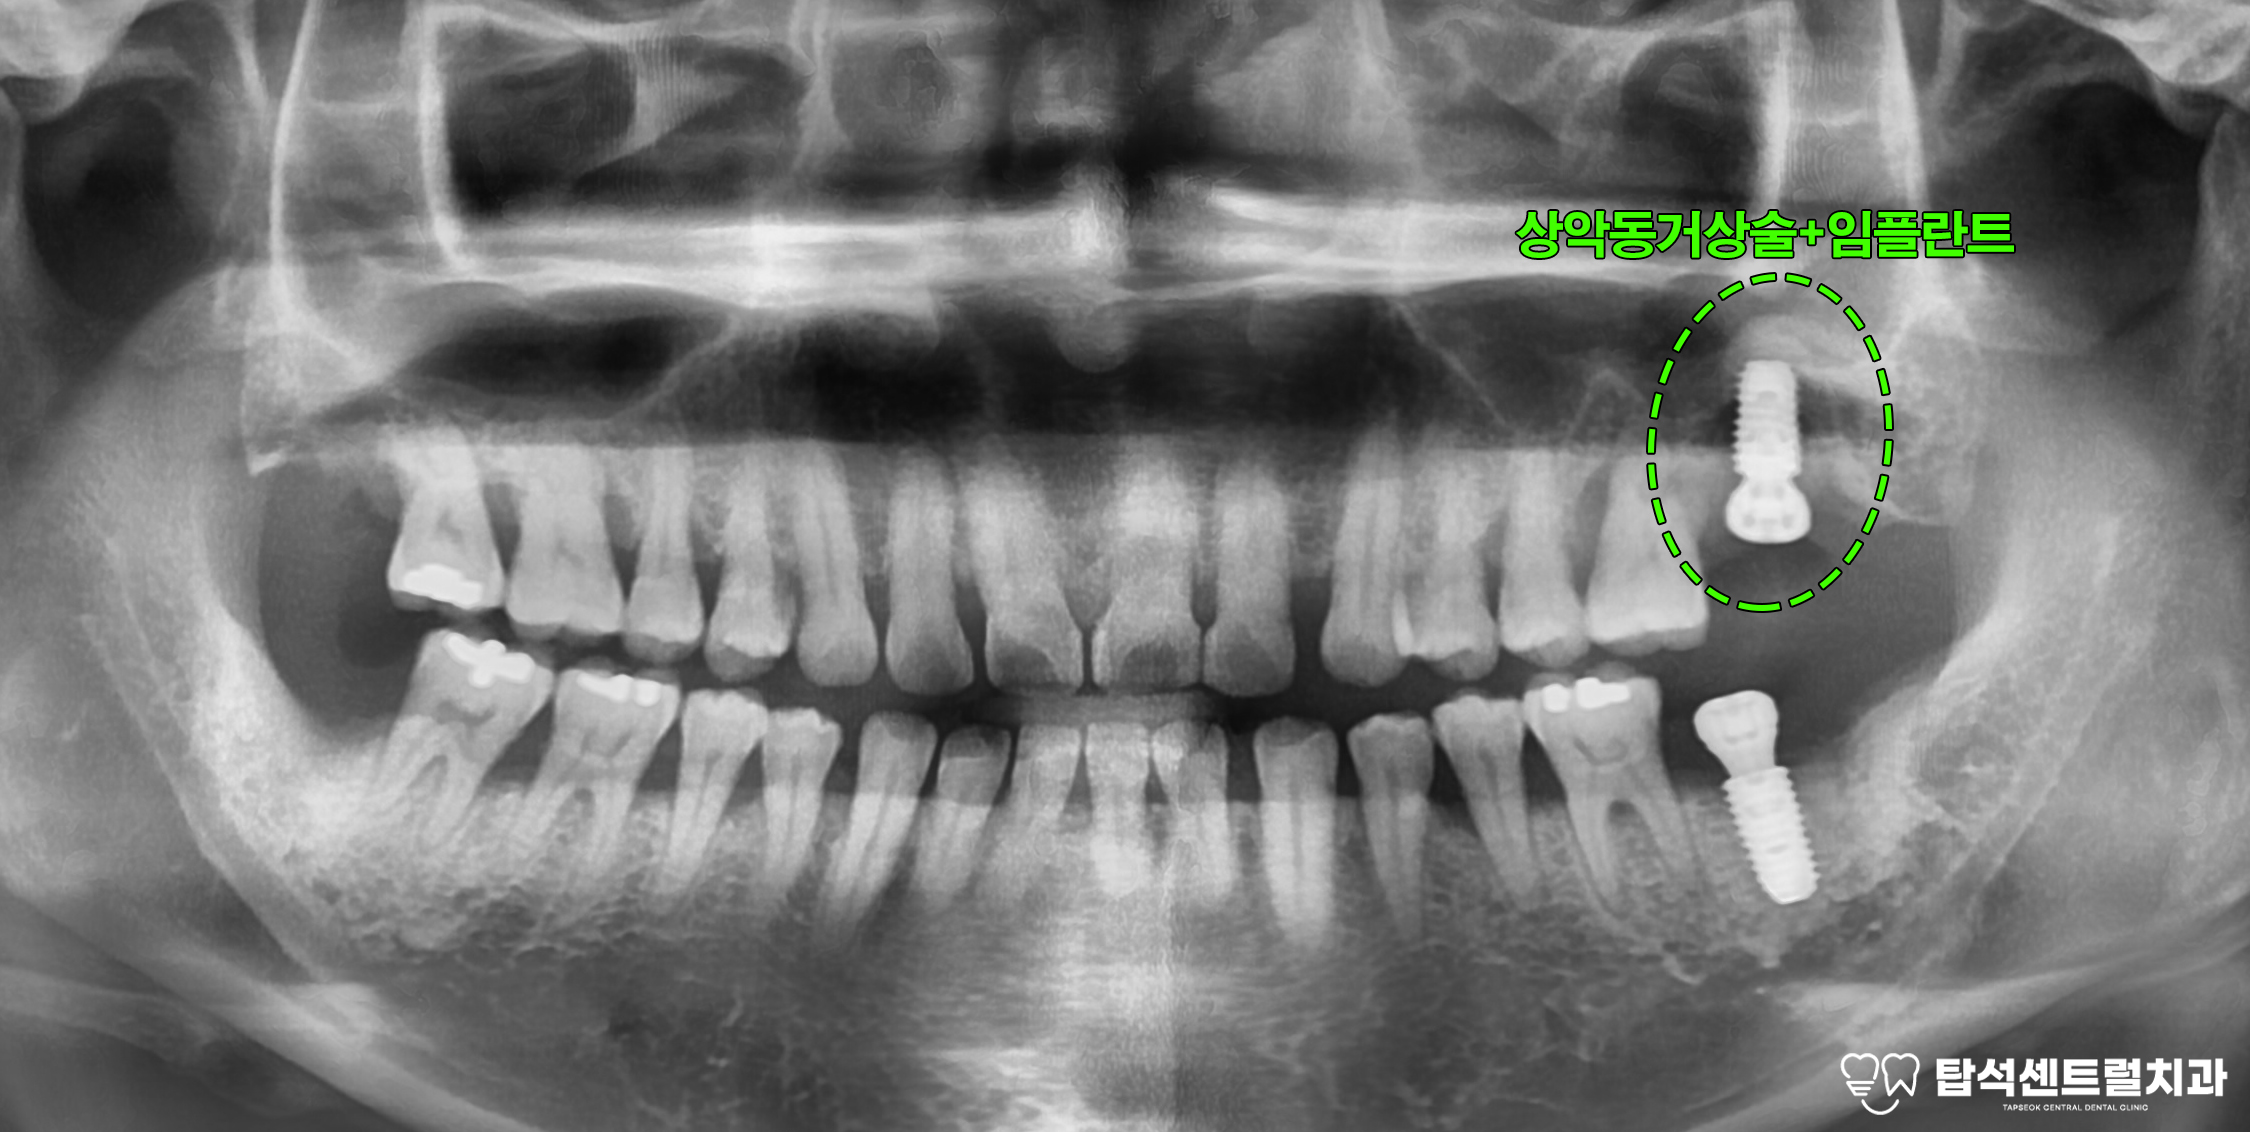

엑스레이 촬영을 통해 구강 상태를

확인하면 치주염으로 인한 전반적인

치조골 소실이 관찰되는 경우가 적지 않습니다.

치조골은 이를 지탱하는 뼈 조직으로

이 부분이 손상되면

치아 동요도가 증가하게 됩니다.

27번과 37번처럼

심한 동요도와 함께

통증을 호소하는 상황에서는

발치를 고려해야 되는 단계에

이르게 됩니다.

약 3개월의 치유 기간이 지나면

위턱에 픽스처를 심을 차례입니다.

발치와 보존술로 어느 정도 치조골을 보존했지만

상악동저까지의 골 높이가 충분하지 않은 경우

상악동 거상술이 필요합니다.